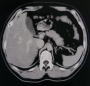

![]() スパイラルX線CTスキャナー 全身のCT映像が見られます。 肝臓、胆嚢、肺、脳などの強力な診断に・・・ |

![]() 腹部 |